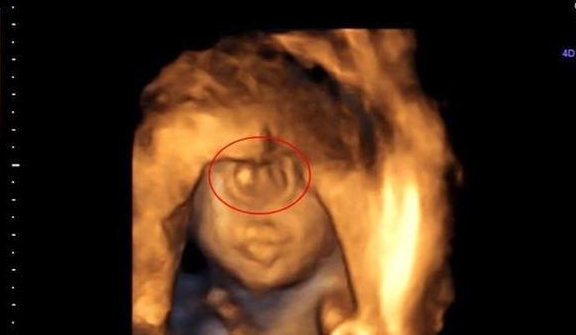

"都怪我"宝妈怀孕看b超以为是双胞胎,孩子出生宝妈后悔_医生_女士